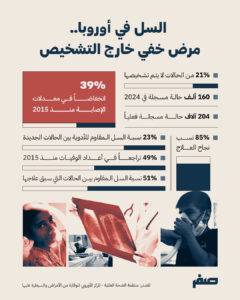

تشير التقديرات إلى أن واحدة من كل خمس حالات سل في إقليم أوروبا لا يتم تشخيصها، ما يعادل نحو 21 بالمئة من إجمالي الحالات، ففي عام 2024 تم تسجيل أكثر من 160 ألف حالة مؤكدة، بينما يقدر العدد الفعلي بنحو 204 آلاف حالة، ما يعني أن آلاف الإصابات تبقى خارج أنظمة الرصد الصحي، وتؤكد هذه الفجوة وجود تحديات في الوصول إلى خدمات التشخيص، إلى جانب ضعف الكشف المبكر في بعض الدول، ما يؤدي إلى استمرار انتقال العدوى داخل المجتمعات، بحسب منظمة الصحة العالمية والمركز الأوروبي للوقاية من الأمراض والسيطرة عليها.

أفادت منظمة الصحة العالمية بأنه رغم انخفاض معدلات الإصابة بالسل في إقليم أوروبا بنسبة 39 بالمئة منذ عام 2015، وتراجع الوفيات بنسبة 49 بالمئة، فإن هذه النتائج لا تحقق الأهداف المرحلية لاستراتيجية القضاء على السل التي تستهدف خفضا أكبر بحلول 2025.

يعتمد العلاج القياسي للسل غير المقاوم على نظام دوائي مدته ستة أشهر باستخدام أربعة أدوية رئيسية، مع نسب نجاح تتجاوز 85 بالمئة، وفي المقابل، تتطلب الحالات المقاومة علاجات أطول وأكثر تعقيدا، وغالبا ما ترتبط بنتائج علاجية أقل كفاءة، ما يزيد من الضغط على الأنظمة الصحية.